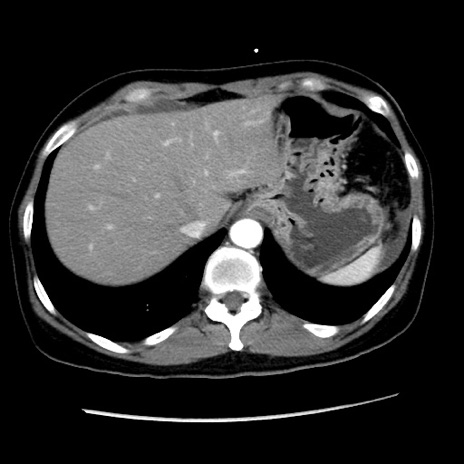

症例10(横断像)

【症例】 50歳代女性

【主訴】 腹痛

【現病歴】前日生レバーを食べた。今朝に排便あり。 昼前に突然発症の腹痛を生じ、当院救急外来を受診した。

【既往歴】 子宮筋腫にてで子宮全摘後

【身体所見】 意識清明、腹部:平坦、軟、下腹部やや左を中心に圧痛・反跳痛あり、筋性防御あり

【データ】WBC 7800、CRP 0.07